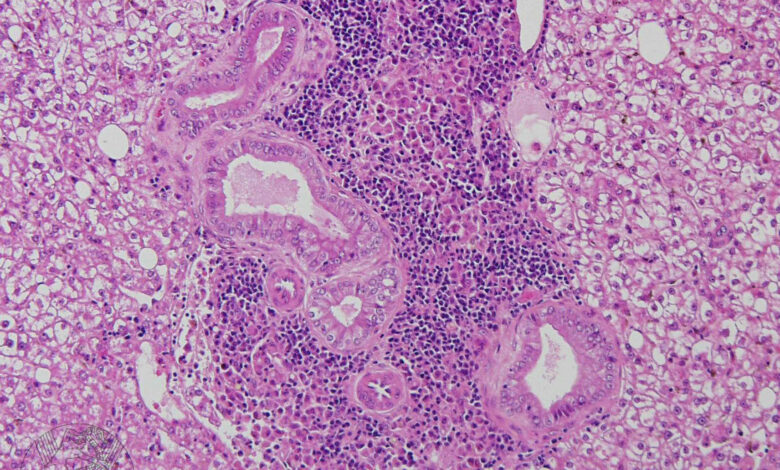

Для точного выявления эндокардита могут быть проведены следующие процедуры: эхокардиография, анализы крови на наличие инфекции, биопсия клапанов сердца.